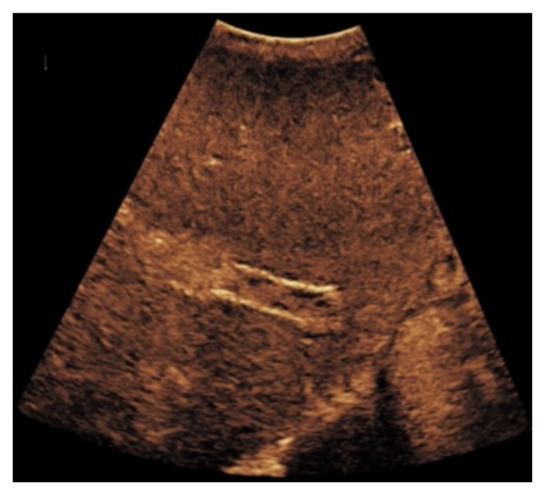

Figure 5. Same patient as in Figure 2. After administration of intravenous contrast, no intraluminal microbubbles can be registered within the transjugular intrahepatic portosystemic shunt compatible with complete occlusion (a,b).